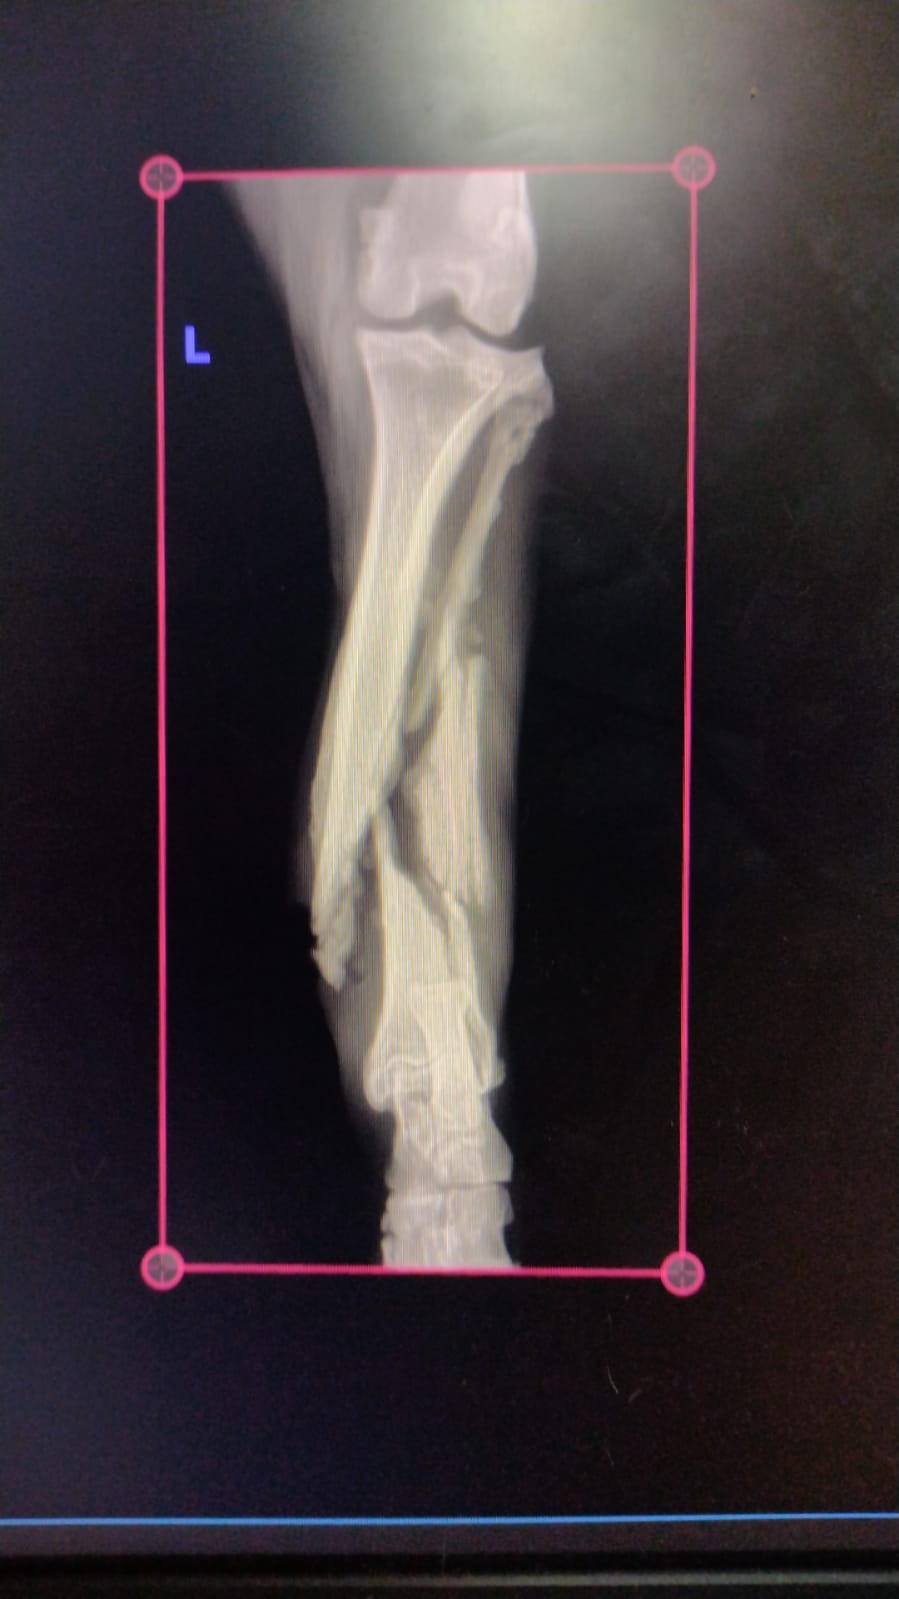

Gambina was found limping helplessly in a park, trembling in pain, after being struck by a car that didn’t stop to help. Her injuries are heartbreaking — she has a fractured rear left leg and tailbone. Because of the trauma, Gambina cannot control her bladder or bowels, and every moment without proper care worsens her condition.

Urgent surgery to repair her fractured leg and spine, and worse case scenario, possible amputation.